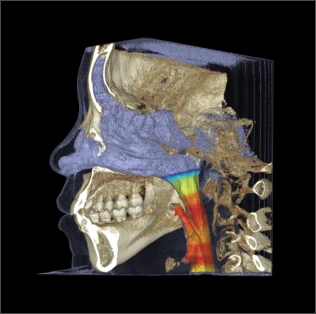

Решения, ориентированные на face-driven dentistry

Всего лишь одно сканирование способно обеспечить быструю и точную обработку данных, гарантируя получение безупречных изображений без искажений. Это открывает вам доступ к всесторонним клиническим перспективам, позволяет уверенно ставить диагнозы и составлять комплексный план лечения, легко направляя вас от начала до конца.

- Анализ дыхательных путей и ВНЧС

- Моделирование ортогнатической хирургии

С помощью RAYSCAN приоритетное внимание уделяется индивидуальности каждого пациента, предлагая настраиваемые объёмы сканирования и изображения с высоким разрешением. Это гарантирует получение чётких диагностических изображений, позволяет ставить верные диагнозы и целенаправленно планировать лечение.